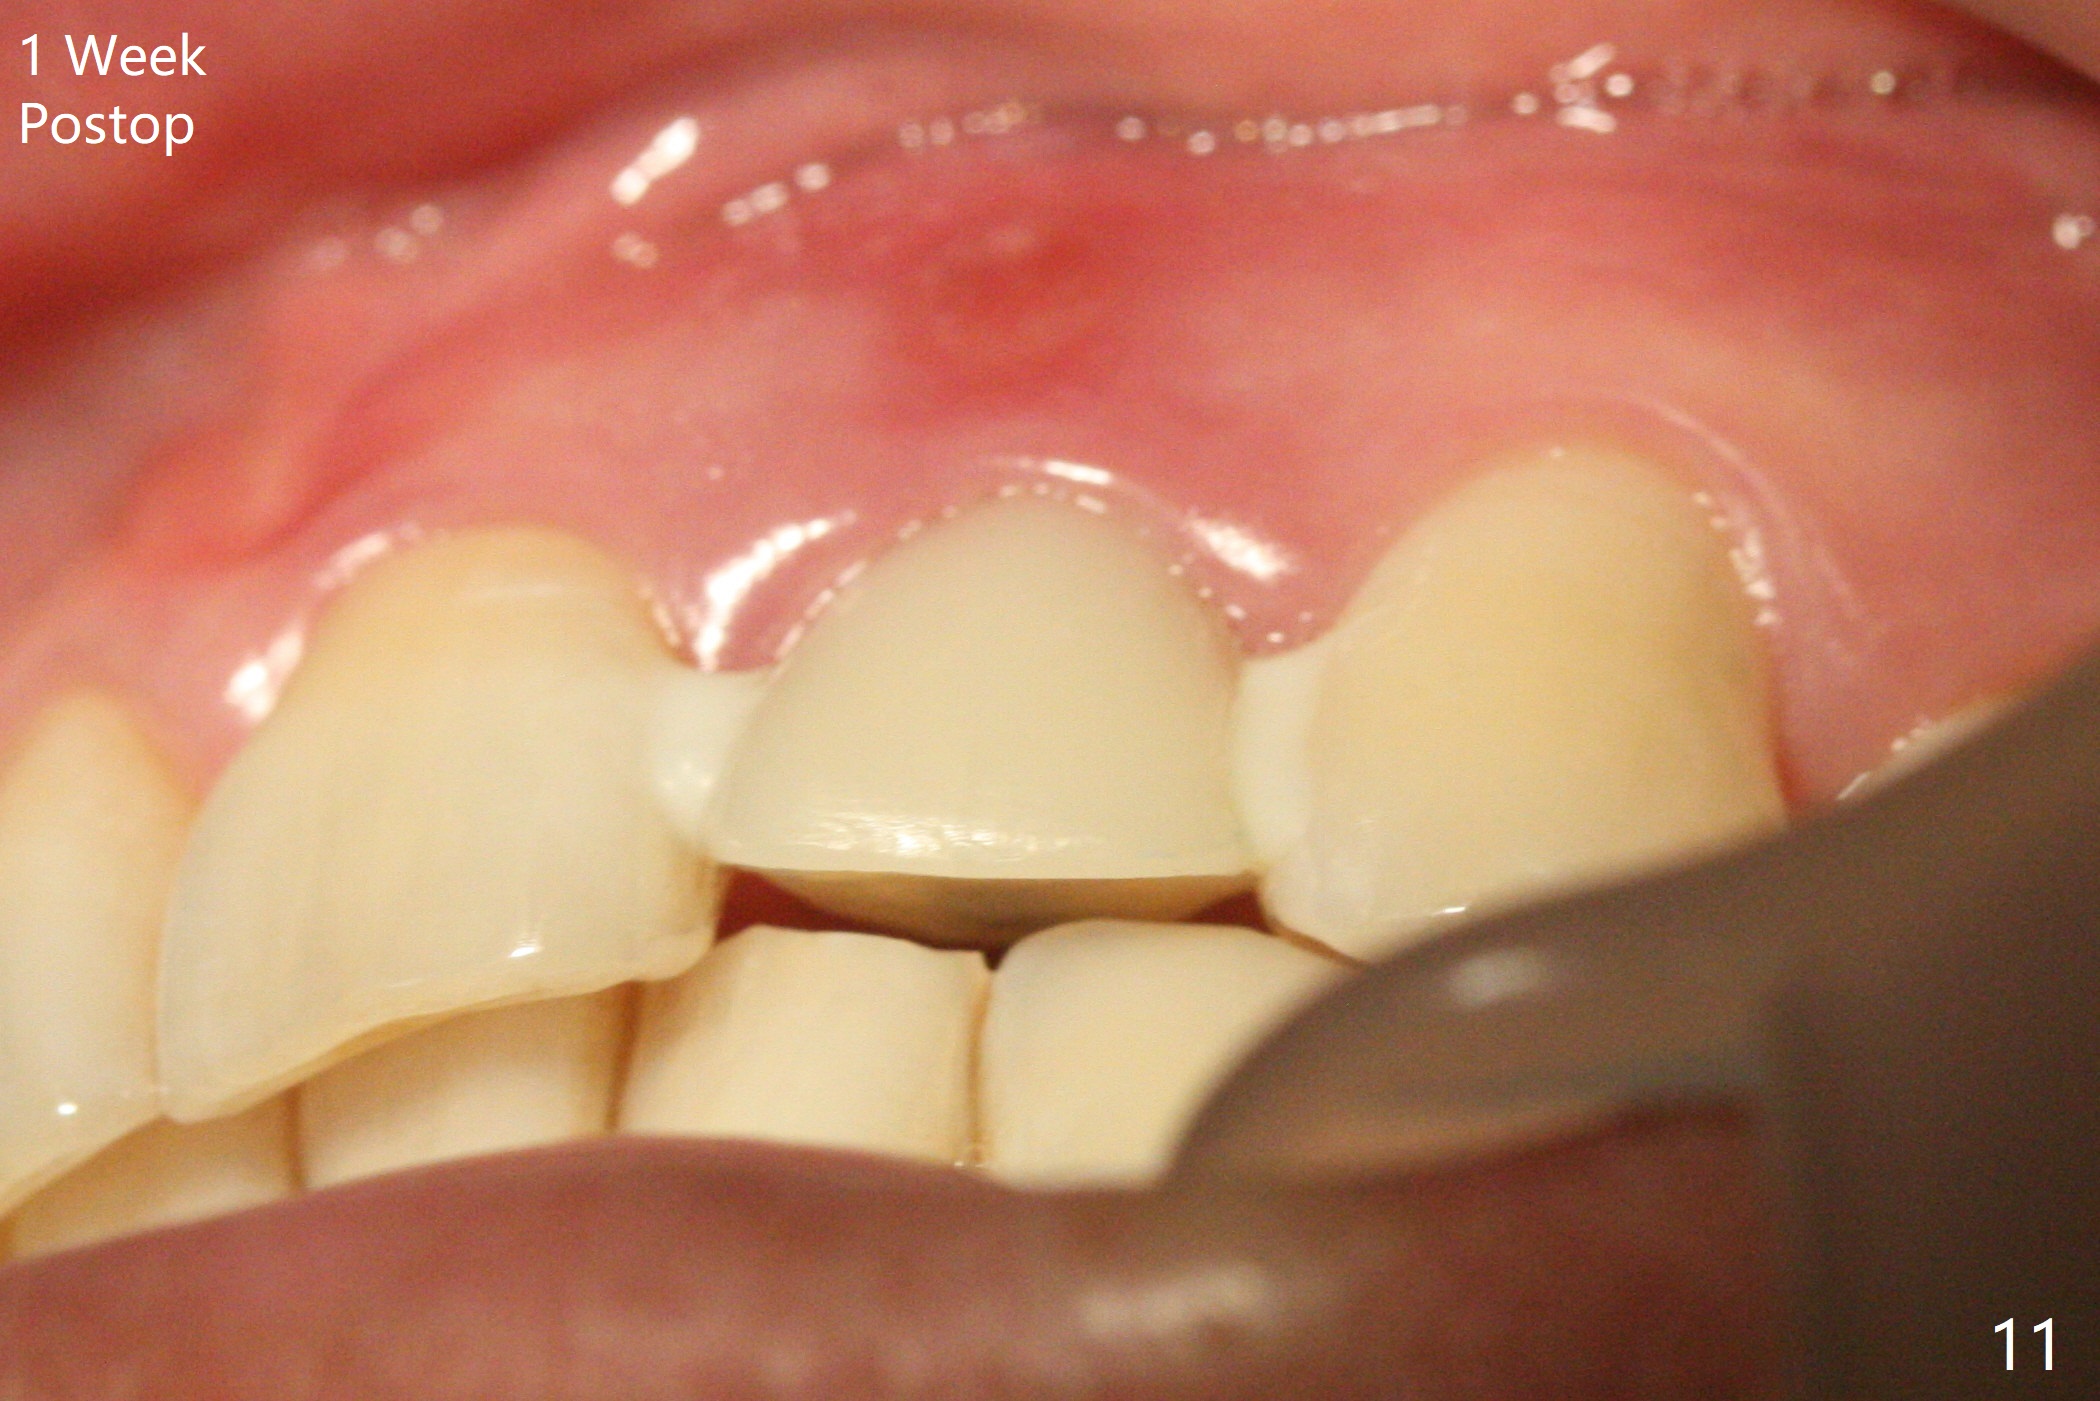

病人回来带来瘘道(图一),不过不会增加难度,病牙去除,它便自动消失。尽管颊侧骨壁完全失去,颊侧牙龈仍丰满(图二),为什么呢?第一,因为粗大牙根存在,第二两旁牙齿,牙槽骨撑着帐篷(侧切牙颊侧牙龈),第三,牙冠。为了防止术后牙龈塌陷,尽量不切开,即刻放置植体(牙根);由于前牙缘故,这次植体不能很大,所以植骨必须过度(over grafting),最后即刻制作临时牙冠,撑住牙龈。这就是所谓每个人进入角色。这个牙根有一种先天性畸形:dens in dent (图三(腭侧观):箭头)。尽管腭侧牙根畸形,腭侧骨壁吸收临床上并不严重,所以钻洞仍偏腭侧。当预定最后钻头还在钻洞时,填入大量粘性骨块(图四:*),细长植体还没有完全卡入鼻底(图五),最后好像可以(图六,七)。植体,骨粉入位(图八),最后临时牙冠出场(图九)。尽管植体小,术后一周临时牙冠仍然可以维持牙龈原有形状(emergency profile,图十:箭头(*:树脂强化牙冠固定))。图十一以不同角度显示瘘道缩小。术后三周取出有些松动的临时牙冠,骨粉虽然还没有被肉芽组织整合,但是显得正常,周围牙龈健康(图十二)。术后4个月牙龈形态正常(图十三),没有触痛;颊侧骨板轻度凹陷(图十四);骨粉仍在原位(图十五)。术后7个月骨粉仍在原位(图十五,十六,但是冠部密度减低(可能骨粉流失,需要牙周或者树脂敷料保护)),没有螺纹暴露。但是牙冠边缘暴露,说明牙龈收缩(图十七,与图十三对比),颊侧骨板仍塌陷(图十八)。插入龈线取得多个目的:修整基台边缘,取模,颊侧牙龈推向颊侧,有利于即将衬里牙冠龈缘进入龈下(图十九)。取模后牙冠边缘(图二十:<)衬里,然后修整,变窄,以便插入龈下,促进颊侧牙龈下降(图二十一,二十二)。术后8个月牙冠粘固前牙龈健康(图二十七,八),牙冠(图二十九)固位后,病人满意(图三十),咬合调整(图三十一),注意腭侧粘固粉流出通道(<)。